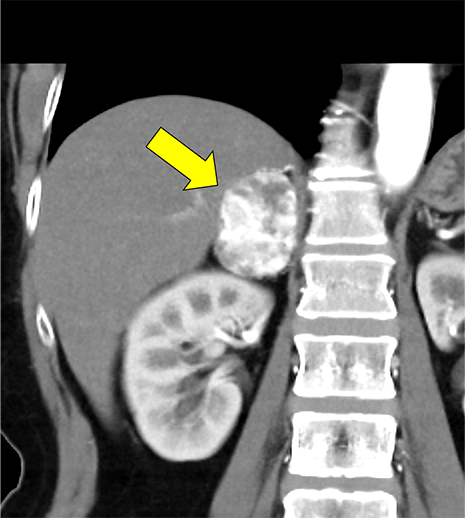

本例は、偶発的に指摘された右副腎腫瘍である。高血圧はあるが内服せず経過観察されている患者で、1cm/5年程度の非常に緩徐な増大を示す多血性の腫瘍を認める。腫瘍はI-123MIBGシンチ陰性であり、内分泌内科での精査においてもホルモン産生を疑う所見に乏しく、褐色細胞腫よりも海綿状血管腫が疑われていた。しかし、増大傾向があり破裂や出血のリスクなども考慮されて手術の方針となった。手術中に血圧の変動を認め、病理で褐色細胞腫の診断となった。

本例の画像所見として、褐色細胞腫としてダイナミック造影の濃染パターンは典型的ともいえたが、大きさの割に変性が乏しい点、MIBGシンチでの核種集積に乏しい点、ホルモン産生に乏しい点など非典型的な要素が複数存在し、海綿状血管腫を除外しきれなかった。なお、褐色細胞腫はRET遺伝子変異による多発性内分泌腺腫症(multiple endocrine neoplasia;MEN)type 2A・2B、VHL遺伝子によるvon Hippel-Lindau病、NF1遺伝子による神経線維腫症1型に生じることが知られているが、これらの疾患を想起させるような他病変は本例には見つかっていない。